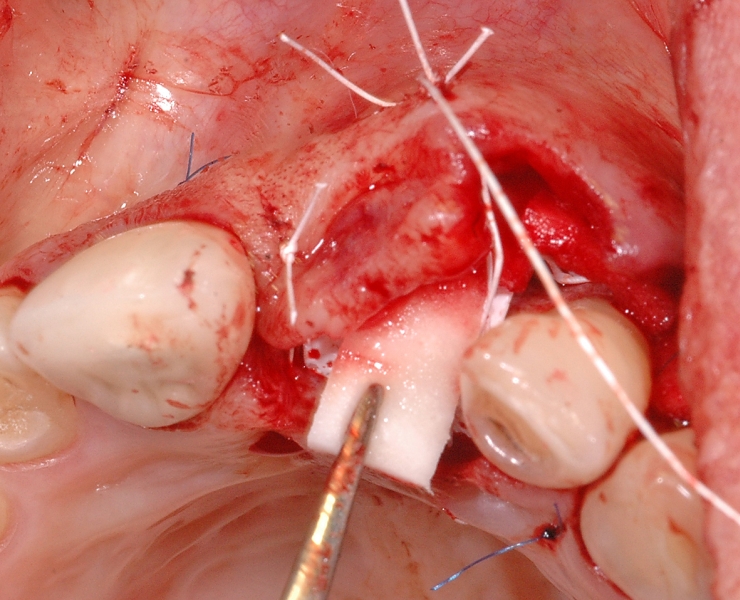

8/18 - Soft tissue thickening of the buccal side with mucoderm® and recession treatment of tooth 23GBR together with soft tissue augmentation with mucoderm® and maxresorb® - Dr. S. Scherg

9/18 - Additional placement of mucoderm®, crestally and linguallyGBR together with soft tissue augmentation with mucoderm® and maxresorb® - Dr. S. Scherg

10/18 - Fixation of mucoderm® and suturing of the flapGBR together with soft tissue augmentation with mucoderm® and maxresorb® - Dr. S. Scherg